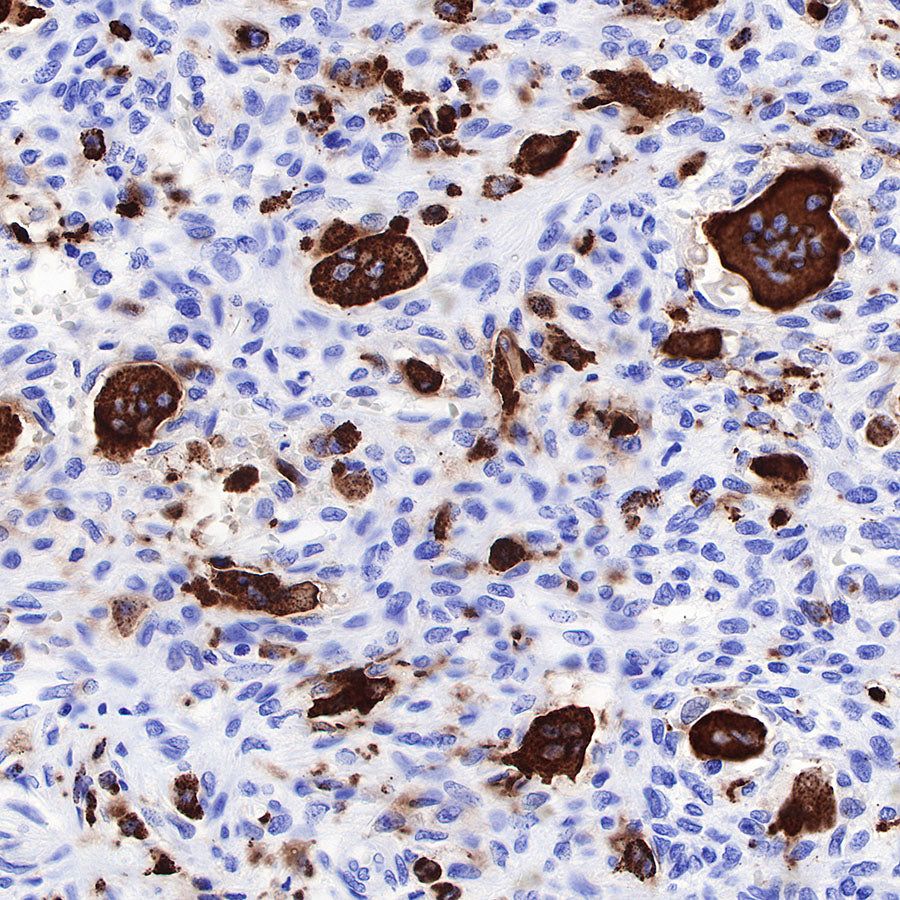

IHC shows positive staining in paraffin-embedded human giant cell tumor of bone. Anti-CD68 antibody was used at 1/1000 dilution, followed by a HRP Polymer for Mouse & Rabbit IgG (ready to use). Counterstained with hematoxylin. Heat mediated antigen retrieval with Tris/EDTA buffer pH9.0 was performed before commencing with IHC staining protocol.